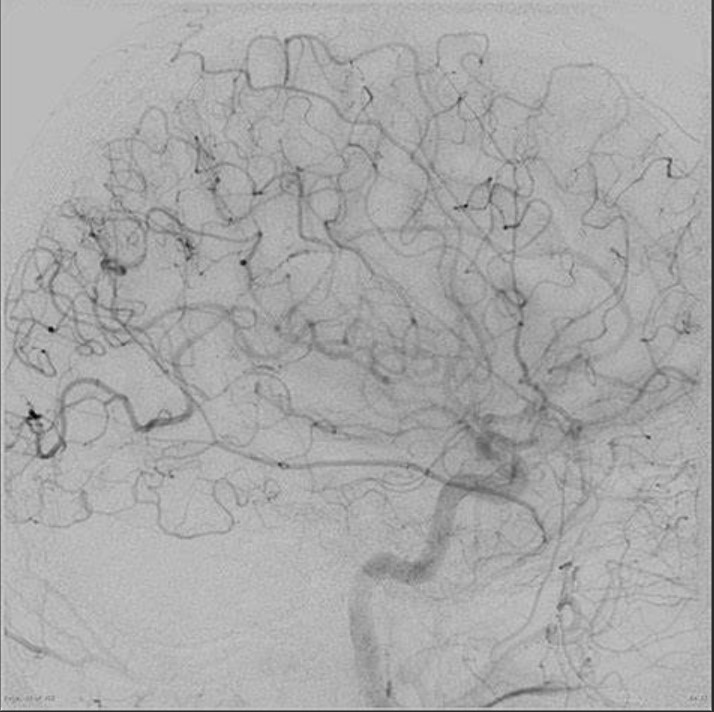

모야모야병은 뇌혈관 질환 중 하나로, 양쪽 내경동맥 앞가지, 중간가지, 또는 뒤가지가 점진적으로 좁아지고 막히는 질환입니다. 일본어로 '연기가 피어오르는 것'을 뜻하는 모야모야(もやもや)라는 단어에서 유래했듯이, 뇌혈관 조영술 영상에서 혈관이 뿌연 연기처럼 보이는 것이 특징입니다.

뇌혈관 조영술

뇌혈관의 상태를 확인하는 가장 정확한 검사입니다.

• 혈관 협착 또는 폐쇄 여부를 확인

• 모야모야 혈관망의 형태와 범위를 파악